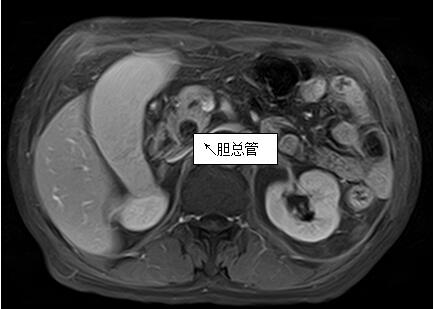

69歲王姓患者,因“發(fā)現(xiàn)無(wú)痛性黃疸1月”入院,根據(jù)患者病史,患者診斷傾向于壺腹部腫瘤所致梗阻性黃疸。予以完善腹部CT及上腹部MRI加MRCP均顯示肝內(nèi)外膽管擴(kuò)張,未發(fā)現(xiàn)明顯膽管,胰腺及十二指腸乳頭部腫瘤,且患者CA199正常。以前醫(yī)院未引進(jìn)超聲內(nèi)鏡,這類(lèi)患者到此就遇到診斷瓶頸。此患者經(jīng)過(guò)消化內(nèi)科張丹霞副主任醫(yī)師完善超聲內(nèi)鏡檢查后,可以清楚顯示膽總管下段壁內(nèi)軟組織占位。患者通過(guò)超聲內(nèi)鏡檢查診斷明確,轉(zhuǎn)至肝膽外科行手術(shù)治療。

上腹部MRI圖片